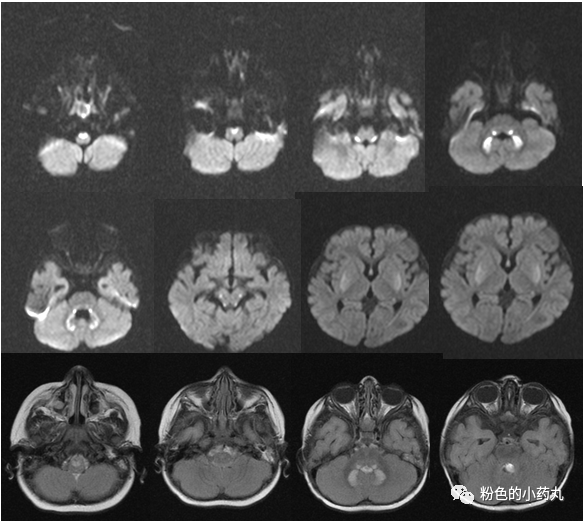

因遗传特征不同MRI通常呈异质性。一般来说,病灶分布对称。可分为三型: 基底节型、脑干型及白质型。

T2/FLAIR高信号,累及基底节中以壳核最多见,累及丘脑中以背侧丘脑内侧近第三脑室最多见。文献报道,双侧对称的壳核受累是必备的特征,尾状核、苍白球及丘脑可同时受累,但绝不会在壳核不受累的情况下单独出现。脑白质、皮层及小脑受累少见,病变范围较广可累及胼胝体和内囊。

T1常表现为低信号,但可见部分高信号,有一定强化。

DWI 的信号变化在时间分布上呈多样性,急性期DWI 病变可见弥散受限。

图 病例2